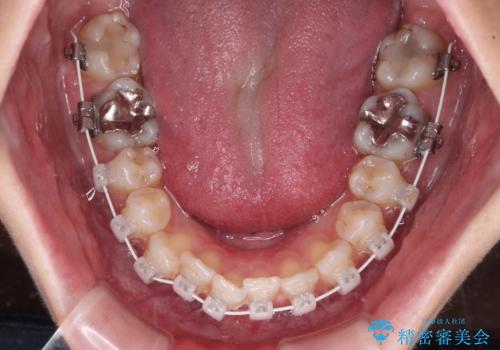

- 歯並びと虫歯をきれいにしたいとのことで来院された患者様です。

楽して短期間で歯列を整えたいとのことで、ワイヤー装置を用いて矯正治療を行い、矯正治療後に下顎の虫歯はセラミックインレー、上顎はPGAインレー(ゴールドインレー)、根管治療を行う歯についてはオールセラミッククラウンにて補綴治療を行うこととしました。

矯正治療は8ヶ月ほどで終了し、速やかに虫歯治療に移行することができました。

保険治療で用いる樹脂(コンポジットレジン)で行った虫歯治療は、周辺が変色して汚くなっていましたが、下顎はセラミックインレーで審美的に、上顎はPGAインレーで歯に負担の少ない治療を行うことができました。